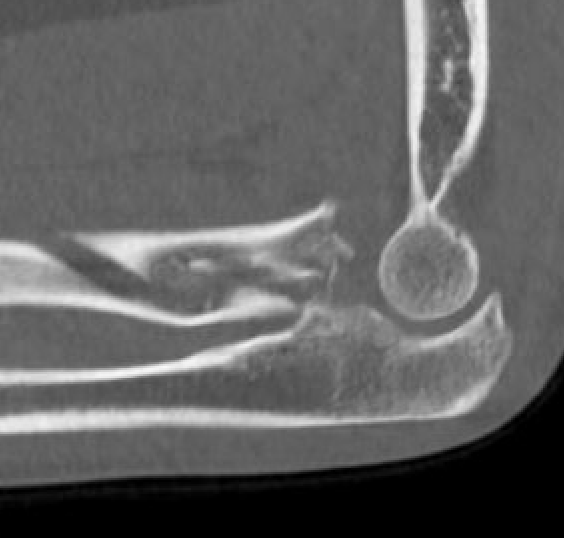

Completely displaced radial neck fracture

ORIF with plates